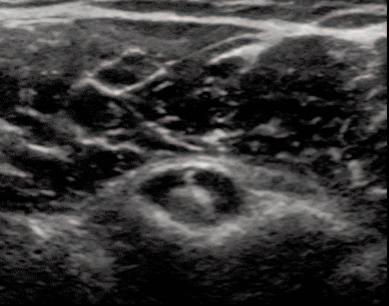

Figure 2a: Normal Tendon-Short Axis View. LHBT is located deep within the inter-tubercular groove and viewed as a bright hyperechoic defined tendon. It is easily seen see between the bony greater and lesser tuber cles. The thin band of bright tissue overlying the top of the bicep’s tendon is the transverse humeral ligament.

TENDON PATHOLOGYFigure 3a: Effusion and edema are seen as an area of hypoechoic signal within the tendon sheath surrounding the LHBT. The anechoic ring is known as a “halo sign” on a SAX view. This edema could be either a tenosynovitis or a capsulitis. The LAX will be the differential view.